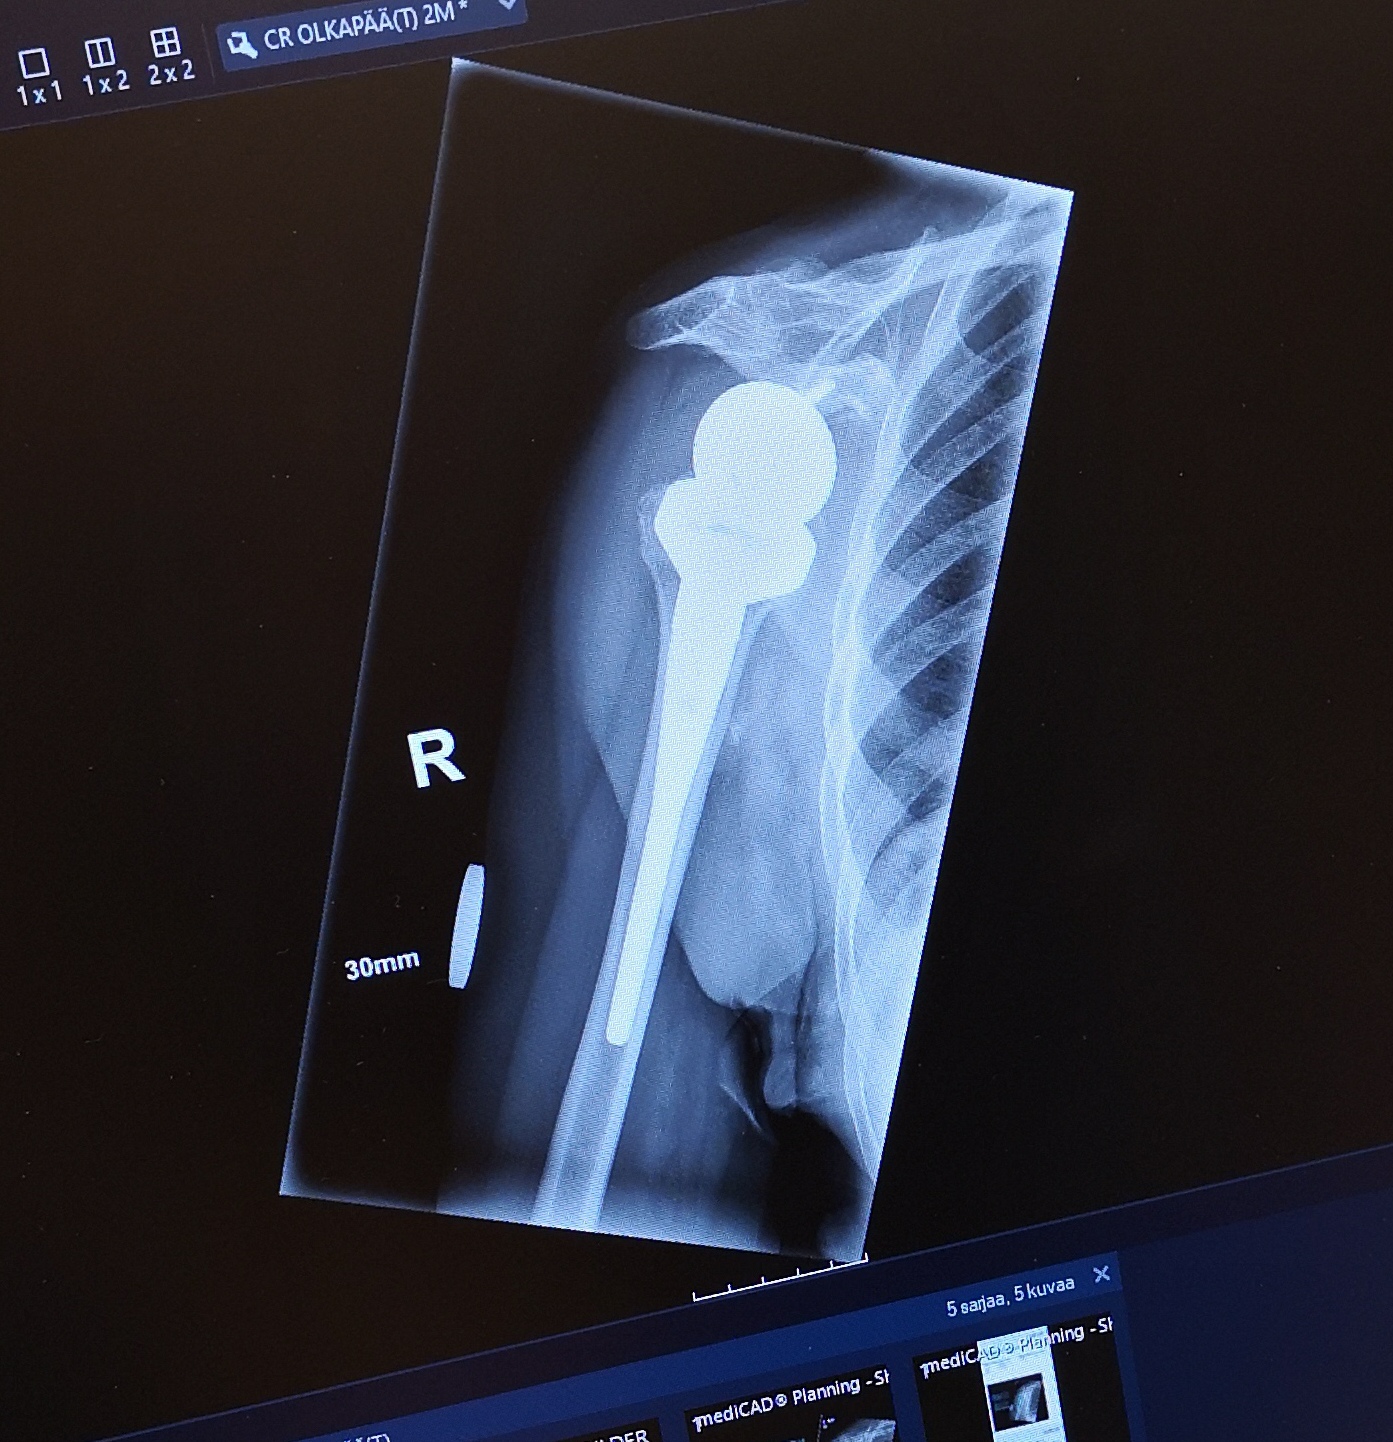

Systeeminen skleroosi (SSc), morfea, "skleroderma"